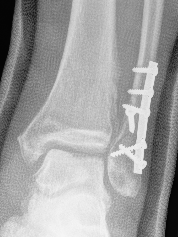

Fibular nail

Plate versus nail

Attia et al Foot Ankle Surg 2022

- meta-analysis of plate versus nail for fibular fractures

- 4 comparative studies and 260 patients

- increased functional outcomes with nail

- complication rate: plate 29% nail 8%

- infection rate: plate 8% nail 0%

- re-operation rate: plate 8% nail 5%